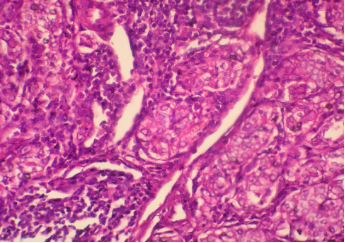

HISTOPATHOLOGY

Section H and E x400. Mass in the wall of the small intestine in a 72 year old male patient who presented with frequent diarrhoea. Make you diagnosis.